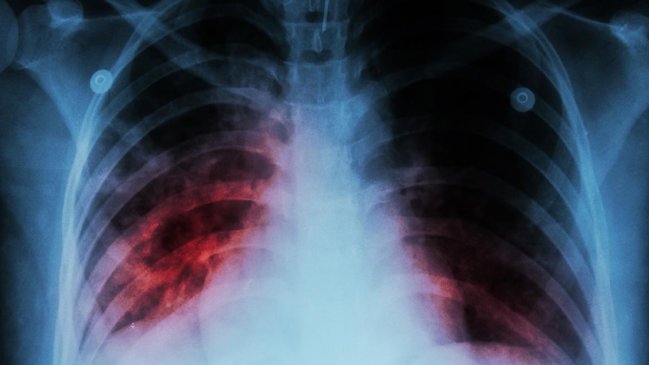

Casi 50 trabajadores de la salud se infectaron de tuberculosis en Venezuela

Referencial

Al menos 46 trabajadores sanitarios del sector público de Venezuela se infectaron de tuberculosis entre enero y junio de este año, según un reporte de la Encuesta Nacional de Hospitales (ENH) publicado este jueves y elaborado por la ONG Médicos por la Salud.

La organización señaló que los casos se tratan de "diagnósticos presuntivos clínicamente y no de casos confirmados", pues en Venezuela "no hay reporte semanal epidemiológico desde 2015".

El reporte no confirma que los sanitarios se infectaron en sus lugares de trabajo, pero sí reitera el deterioro de la red hospitalaria pública, en la que escasean medicamentos y elementos como mascarillas y guantes.